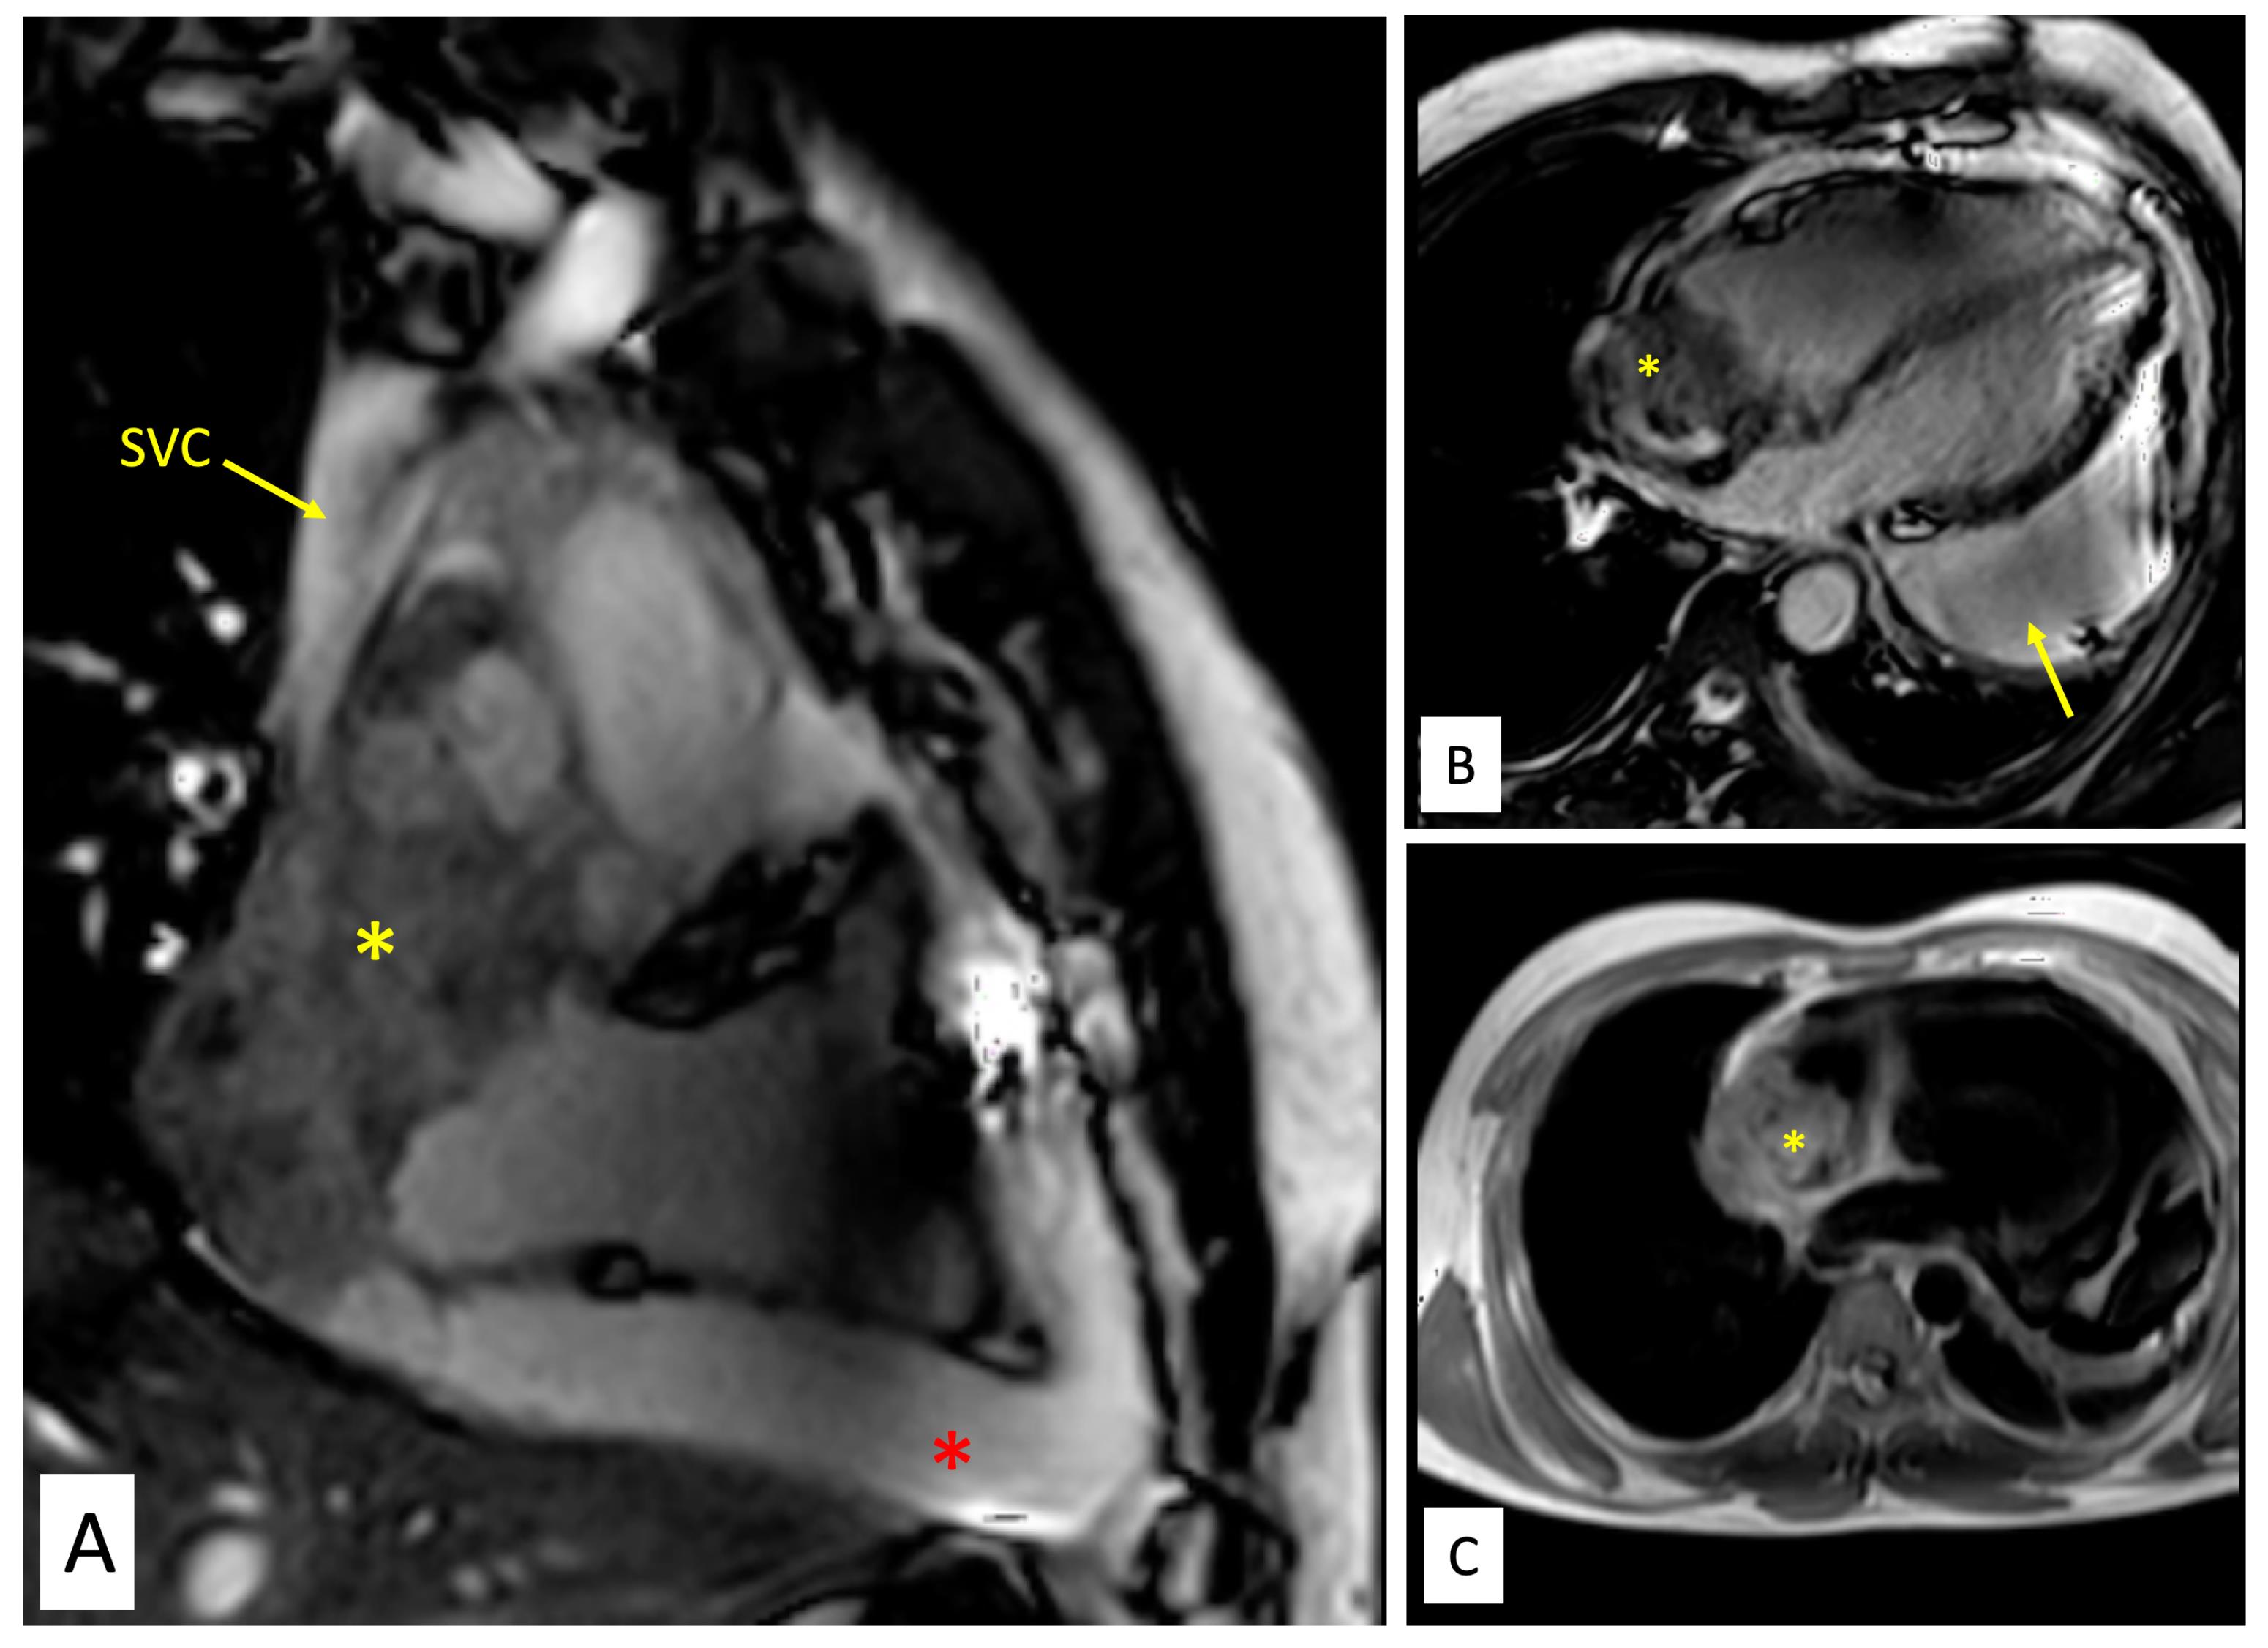

Figure 2.

Magnetic resonance imaging of the tumour. A. Balanced steady state free precession (SSFP) TRUFisp image in coronal view shows craniocaudal extent of the mass(yellow asterisk) spanning from superior vena cava (SVC)-right atrial (RA) junction cranially to acute margin of the heart. The mass is seen infiltrating into SVC (yellow arrow). Large pericardial effusion is also seen (red asterisk). B. Balanced steady state free precession (SSFP) TRUFisp image in horizontal long axis shows heterogeneous hyperintense lobulated mass (yellow asterisk) extending into the right atria and superior vena caval junction. The mass is abutting the anterior wall of RA and interatrial septum. Additionally, asymmetric loculated moderate pericardial effusion is noted (yellow arrow). C. Axial T1 non-fat saturated image reveals heterogeneous signal intensity infiltrative mass (yellow asterisk) centered along anterior right atrial wall involving pericardium and extrapericardial space.

Contrast enhanced cardiac computed tomography (CT) showed an irregular, broad-based, ‘cauliflower like’ mass abutting the lateral wall of RA with a heterogeneous streaky (sun ray) post-contrast enhancement (Figure 1E). There was local pericardial infiltration with associated moderate pericardial effusion. An aggressive mass in RA, metastasis or angiosarcoma, was suspected. There was no evidence of any primary tumor anywhere in chest or abdomen on CT scan. Cardiac magnetic resonance (CMR) imaging showed a T2-hyperintense mass measuring 64 mm x 44mm involving anterolateral wall of RA, with thickening of adjacent pericardium, superiorly invading cavo-atrial junction and extending into the superior venacava (SVC) (Figure 2A-2C). Invasion of SVC favours angiosarcoma over lymphoma; lymphoma usually presents as an insinuating mass without displacement or compression of vascular structures. The rapidly growing mass in the CMR compared to the CT image 1 week earlier, infiltration into pericardium and SVC pointed towards a rapidly growing malignant tumor. ATT was discontinued as there was a lack of improvement in symptoms and imaging evidence of likely malignancy. Positron emission tomography (PET) scan revealed an FDG-avid mass in the RA wall with extension into mediastinal structures and similar uptake in right lower paratracheal, prevascular, paraortic & paracardiac regions (Figure 1F). The mass was seen to infiltrate ascending aorta, pulmonary artery and SVC. It showed areas of photopenia & hypodensity within mass, suggestive of necrosis. No metastasis to distant organs was noted. Patient had further deterioration of dyspnea and in search of a definitive diagnosis, an endomyocardial biopsy was planned after discussion with heart team. The tissue analysis, however, did not yield any malignant cells. After discussion with the family, open biopsy using a lateral thoracotomy approach was performed. A few hours after the procedure, patient had sudden and rapidly progressive shock and worsening of respiratory distress requiring mechanical ventilation. Echocardiogram revealed large pericardial effusion with tamponade, which on aspiration yielded hemorrhagic fluid. With a possibility of active bleed from the vascular tumor or a vessel, a midline thoracotomy was done to localize and stop bleeding. The patient’s hemodynamics worsened during the procedure and he succumbed. Histological examination of the biopsied tissue revealed large areas of hemorrhage with fibrin & necrosis. Preserved areas showed a tumour arranged in sheets and short intersecting fascicles. There were slit like spaces with red blood cells. Tumor cells were moderately pleomorphic, had round-to-oval nuclei with vesicular chromatin, conspicuous nucleoli and moderate amount of cytoplasm. These cells were positive for CD31(membranous) and negative for desmin and PanCK(pancytokeratins) which was suggestive of angiosarcoma.